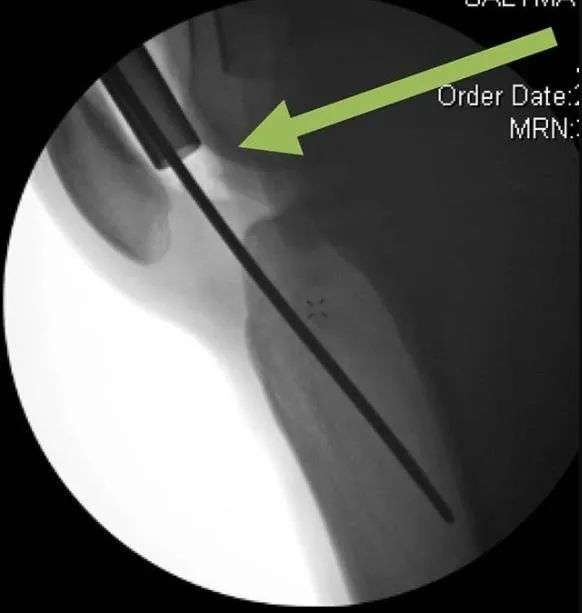

Рис. 9б. Правильное положение проводника — на одной линии с осью большеберцовой кости в передне-задней плоскости и как можно ближе к передней кортикальной поверхности в боковой проекции. Проводник имеет тенденцию перемещаться назад.

Рисунок 9c. В случаях, когда булавку или гвоздь невозможно вставить правильно, блокировка гвоздя или булавки помогает направить гвоздь в правильное положение.